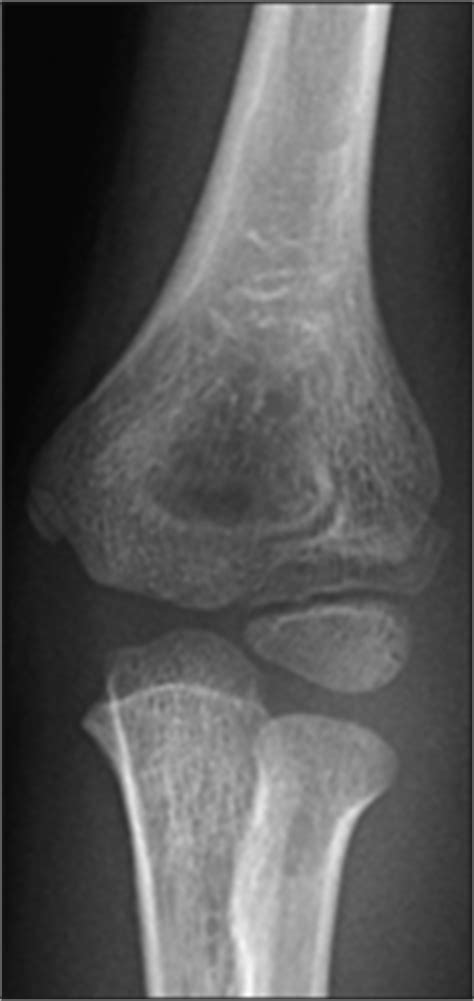

Medial epicondyle fracture | Image | Radiopaedia.org

Medial epicondyle fracture | Image | Radiopaedia.org from images.radiopaedia.org